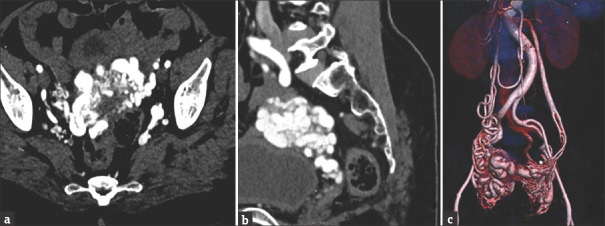

子宫动静脉畸形(UAVM)是一种罕见的发生在绝经后妇女。我们对文献的回顾显示,在这一人群中,只有少数记录在案的UAVM病例。这些患者的治疗选择包括子宫动脉栓塞(UAE)、医疗管理和子宫切除术。我们遇到了一个54岁的妇女,绝经9年,在绝经前3个月有出血史。影像学检查证实了UAVM的存在。尽管尝试了阿联酋手术,但手术失败了,因此决定进行子宫切除术,并一丝不苟地注意尽量减少失血。值得注意的是,在绝经后妇女中,子宫切除术可能并不总是能取得良好的结果,因此强调子宫切除术作为一种安全的替代治疗选择,没有任何术中过多出血。

Uterine arteriovenous malformation (UAVM) is an infrequent occurrence among postmenopausal women. Our review of the literature revealed only a few documented cases of UAVM in this demographic. Treatment options for these patients encompass uterine artery embolization (UAE), medical management, and hysterectomy. We encountered a case involving a 54-year-old woman, postmenopausal for 9 years, who presented with a history of postmenopausal bleeding over the preceding 3 months. Imaging studies confirmed the presence of UAVM. Despite an attempted UAE, the procedure proved unsuccessful, leading to the decision to perform a hysterectomy with meticulous attention to minimizing blood loss. Notably, UAE may not consistently achieve favorable outcomes in addressing UAVM in postmenopausal women, thereby underscoring the consideration of hysterectomy as a safe alternative - treatment option without any excessive intraoperative bleeding.